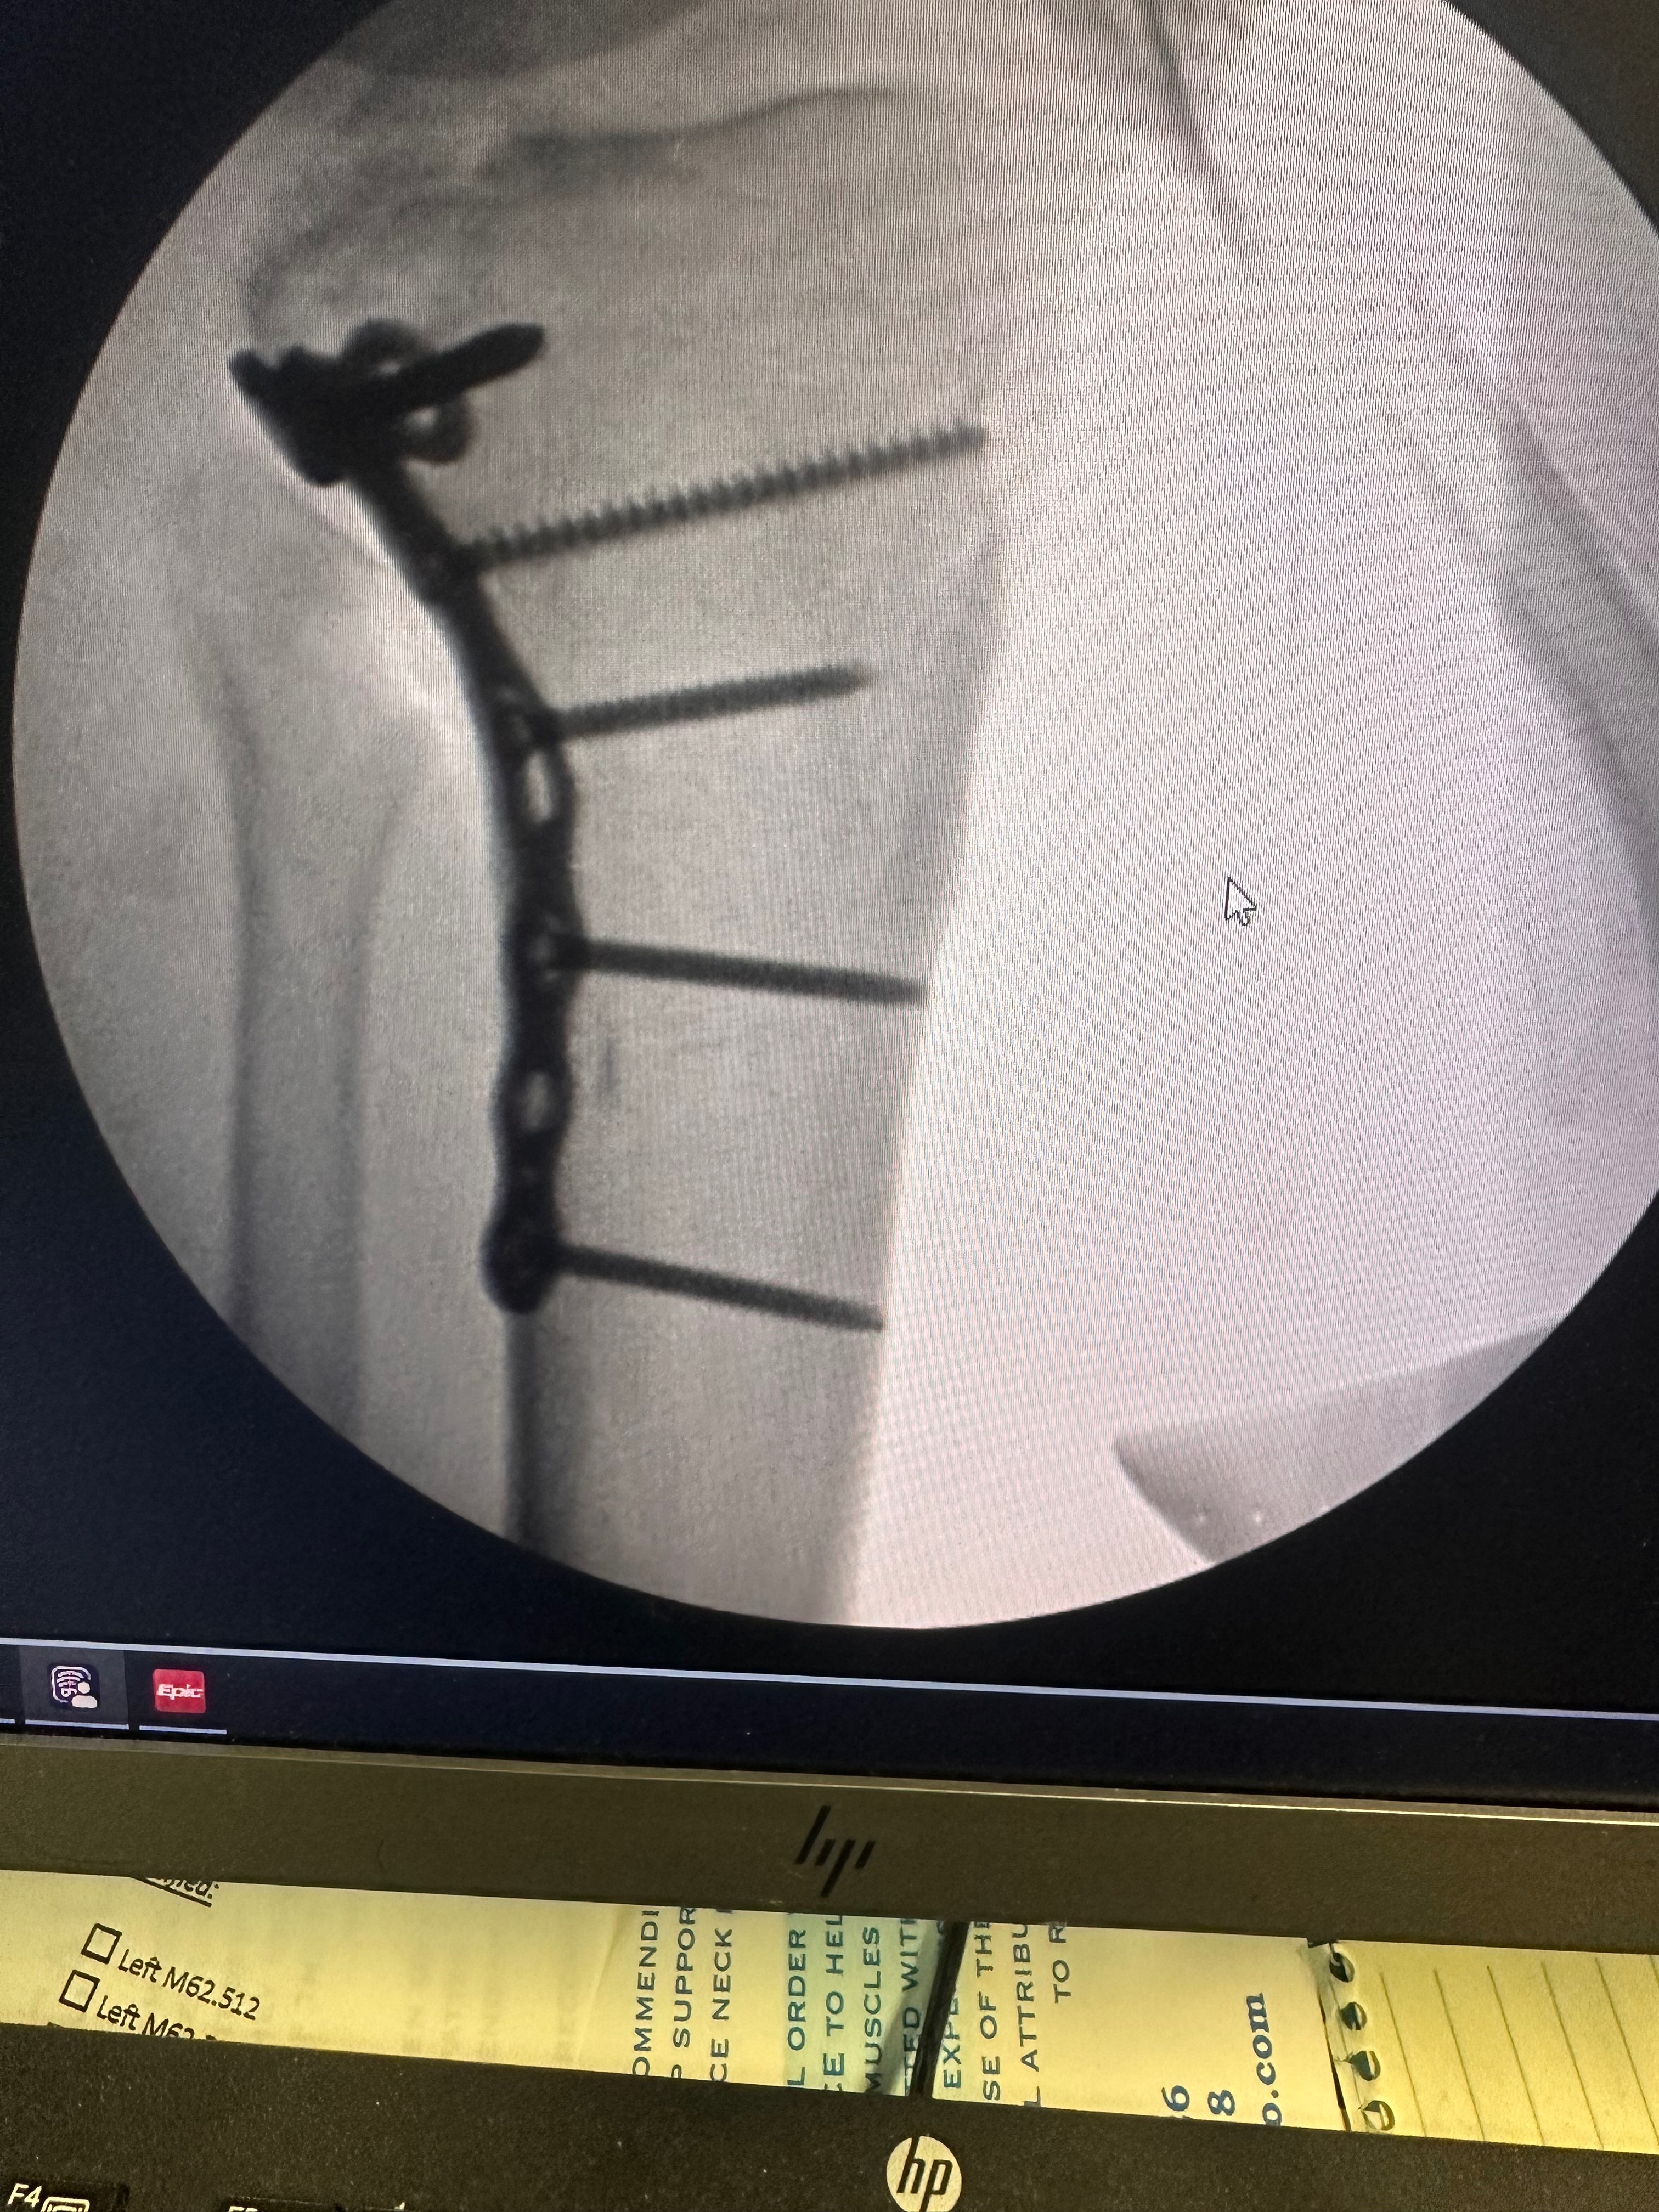

Hello, my name is Dream Smith, and I need urgent help to walk again. Four months ago, I suffered a traumatic leg injury that completely changed my life. I fractured my tibia and tore my ACL - both requiring surgery. I had my first surgery to repair the fracture with permanent rods and screws. But I was told immediately that I would also need ACL reconstructive surgery, or else I could become permanently disabled.